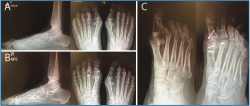

Mostramos una imagen clínica preoperatoria de la luxación MTF y la desviación medial en el plano horizontal del 2.º dedo en la Figura 15A y un control postoperatorio a los 3 meses en la Figura 15B (Vídeo).

En la Figura 16A se muestra el estudio radiológico de frente y de perfil en carga preoperatorio y en la Figura 16B el control postoperatorio a los 6 meses de evolución con reducción de la articulación MTF.

En la Figura 16C puede verse la proyección oblicua pre- y postoperatoria a los 6 meses de evolución con buena reducción MTF.

Figura 15. A: imagen clínica preoperatoria mostrando la luxación metatarsofalángica (MTF) y desviación medial en el plano horizontal del 2.º dedo; B: control postoperatorio a los 3 meses con buena reducción y alineación MTF.

Figura 16. A: estudio radiológico de frente y de perfil en carga preoperatorio evidenciando la luxación metatarsofalángica (MTF) asociada a garra interfalángica proximal (IFP) del 2.º dedo; B: control postoperatorio a los 6 meses de evolución con reducción de la articulación MTF; C: proyección oblicua pre- y postoperatoria a los 6 meses de evolución.